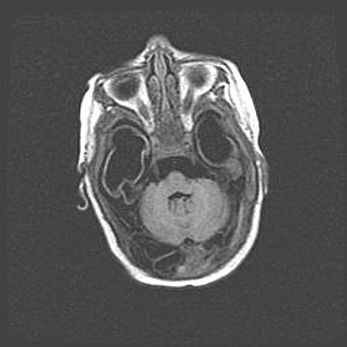

Подострая гематома правой гемисферы мозжечка.

Наружная гидроцефалия.

Возраст: 15 дней

Вес: 3100 г

Пол: женский

Окружность головы: 37 см

Срок гестации: 35-36 недель

При открытой наружной форме гидроцефалии у новорожденных расширяются и переполняются субарахноидные пространства.

Кровоизлияния в мозжечок имеют две клинико-анатомические формы: полушарные гематомы и кровоизлияния в червь.

К появлению этой патологии может привести: повреждения головного мозга, возникающие в результате асфиксии и гипоксии плода при беременности, или травмы во время родов. Редко гематома мозжечка может быть результатом первичной коагулопатии и сосудистой мальформации, диссеминированном внутрисосудистом свертывании, изоиммунной тромбоцитопении.